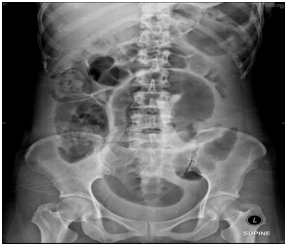

A 29-year-old lady, without significant medical history, presented to our hospital emergency department with 3 days history of constipation associated with generalized abdominal pain, nausea and vomiting. On further history taking, patient had a traditional massage done due to lower abdominal pain. On examination, the abdomen was distended with diffuse marked tenderness without rigidity or guarding; no hernias or masses were noted, bowel sound was sluggish. Digital rectal examination reveal normal finding. We proceeded with imaging. Abdomen X-ray shows large bowel loops are dilatation measuring about 6cm and an ultrasound abdomen was done and there were free fluid presence in the abdomen and pelvis. Our impression on that time was perforated appendicitis. We proceeded with exploratory laparotomy and the intraoperative findings shows gangrenous sigmoid colon secondary to volvulus caused by broad ligament tear and twisted left ovarian cyst. We proceeded with a Hartmann's procedures. Post operative was uneventful and patient was discharge home at day five post operation (Figures 1–4).

Figure 1 Radiological investigation abdominal x-ray shows a large bowel loops are dilatation measuring about 6cm.